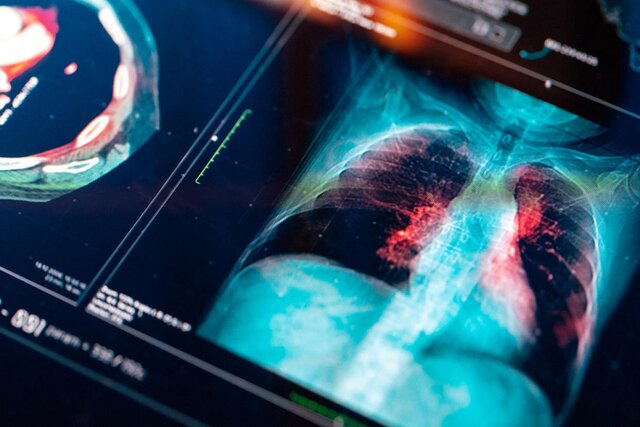

به گزارش روز برتر ، متخصصان سلامت، با ارائه دادههای حاصل از روشهای تصویربرداری مرسوم به این هوش مصنوعی، میتوانند از این مدل برای تشخیص علائمی از بیماری استفاده کنند که در غیر این صورت ممکن است مورد توجه قرار نگیرد.

به نقل از اکستریمتک، به طور معمول، تصاویر حاصل از سونوگرافی، سیتی اسکن، روشهای امآرآی و سایر روشها به متخصصان انسانی فرستاده میشود، که هر تصویر را به دقت بررسی کنند. دستههای سلولی غیرمعمول، تغییر جزئی در شکل سلولهای پوستی، مایعی که میتواند نشان دهنده عفونت ریه و غیره باشد مورد بررسی قرار میگیرند. اما ریزترین نشانههای خطر، میتوانند از زیر چشم رادار عبور کنند و احتمال اینکه بیمار ابتلا به یک مشکل خطرناک سلامتی را قبل از پیشرفت متوجه شود، از بین برود. برخی از مراحل شناسایی، مانند شناسایی تومور و نقشهبرداری شکل دقیق آن، توسط گروهای جداگانه انجام میشود و برخی از اکتشافات بالقوه به ناچار از بین میروند.

هدف مدل BiomedParse پر کردن این شکافها با کمک به انسانها در انجام سه مرحله اصلی پردازش تصویر پزشکی یعنی یافتن موارد خطرناک، تشخیص و تقسیمبندی آنها است. Health Futures میگوید که مدل آنها در ۹ روش تصویربرداری بهتر از چشم انسان عمل میکند و با موفقیت به عنوان یک راه حل تجزیه و تحلیل «کلی» برای طیف گستردهای از تخصصها کاربرد دارد.

این تصاویر هوش مصنوعی BiomedParse را قادر میسازد تا جزئیات ریز را از تصاویر سیتیاسکن، امآرآی، اشعه ایکس، فراصوت، آسیبشناسی، فوندوس(پشت چشم)، درموسکوپی، آندوسکوپی و OCT(موج نور) تشخیص دهد.

Health Futures ادعا میکند که هوش مصنوعی BiomedParse با موفقیت سرطان پوست، کیست، عفونت قفسه سینه ناشی از کووید-۱۹ و تومورها را در سراسر بدن شناسایی کرده است. مشخص نیست که آیا این گروه قصد دارد این فناوری را تجاریسازی کند یا خیر. در این میان، سایر مدلهای هوش مصنوعی به متخصصان پزشکی کمک میکنند تا سرطان لوزالمعده، سرطان ریه، سرطان پستان و سایر شرایط تهدیدکننده حیات را شناسایی و پیشبینی کنند.